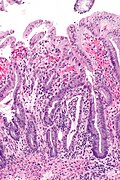

Radiation proctitis. H&E stain. | |

| LM | acute: mucosal changes (necrosis of epithelium, "ghost cells" = cells without nuclei, hemorrhage), submucosa edema with neutrophilic infiltrate, +/-fibrin thrombi; chronic: nuclear atypia - esp. of the stromal cells, fibrosis - esp. of the submucosa |

| LM DDx | inflammatory bowel disease, Infectious colitis, ischemic colitis, pseudosarcomatous stromal changes, sarcoma |

Microscopic

Features - acute:[1]

- Mucosal changes:

- Necrosis of epithelium.

- "Ghost cells" = cells without nuclei.

- Hemorrhage.

- Submucosa edema with neutrophilic infiltrate.

- +/-Fibrin thrombi.

Features - chronic:

- Nuclear atypia - esp. of the stromal cells.

- The epithelium is shed and regenerates... therefore usually does not have the changes.

- Fibrosis - esp. of the submucosa.

DDx:

- Ischemic colitis.

- Inflammatory bowel disease.

- Infectious colitis.